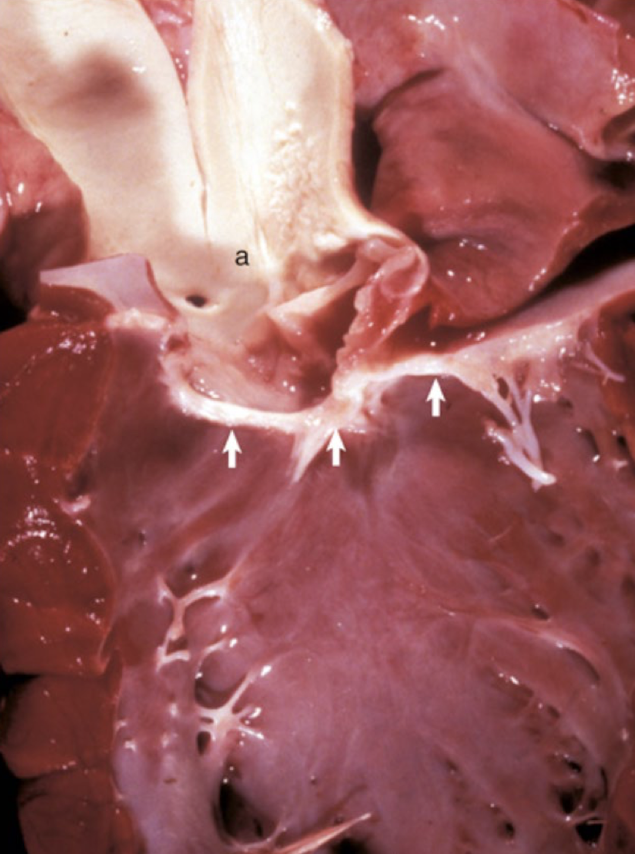

<p>What is this showing?</p>

What is this showing?

tricuspid/mitral valvular dysplasia